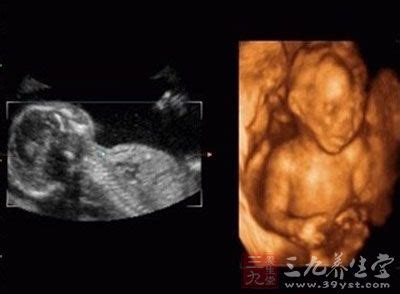

怀孕三个月胎儿男女性别图 三个月男女胎儿性别区别图

怀孕三个月胎儿男女性别图?孕检B超测量数据说明CRL——从胎儿头部到臀部的长度,又称为“头臀长”。妊娠8-11周的这个期间,每个胎儿发育状况还没有太大差异,因此医院往往通过测量CRL来预测预产日。BPD——头部左右两侧之间最长部位的长度,又称为“头部大横径”。当初期无法通过CRL来确定预产日时,往往通过BPD来预测;中期以后,在推定胎儿体重时,往往也需要测量该数据。FL——胎儿的大腿骨的长度,又称为“大腿骨长”。大腿骨是指大腿根部到膝部的长度。一般在妊娠20周左右,通过测量FL来检查胎儿的发育状况。